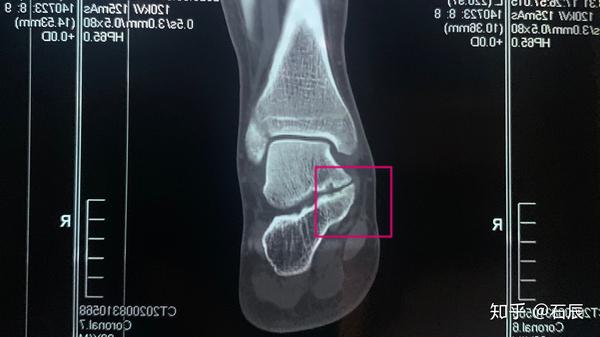

ct三维重建,石院长发现患者脚里跟骨和距骨间长出来了一个像桥一样的